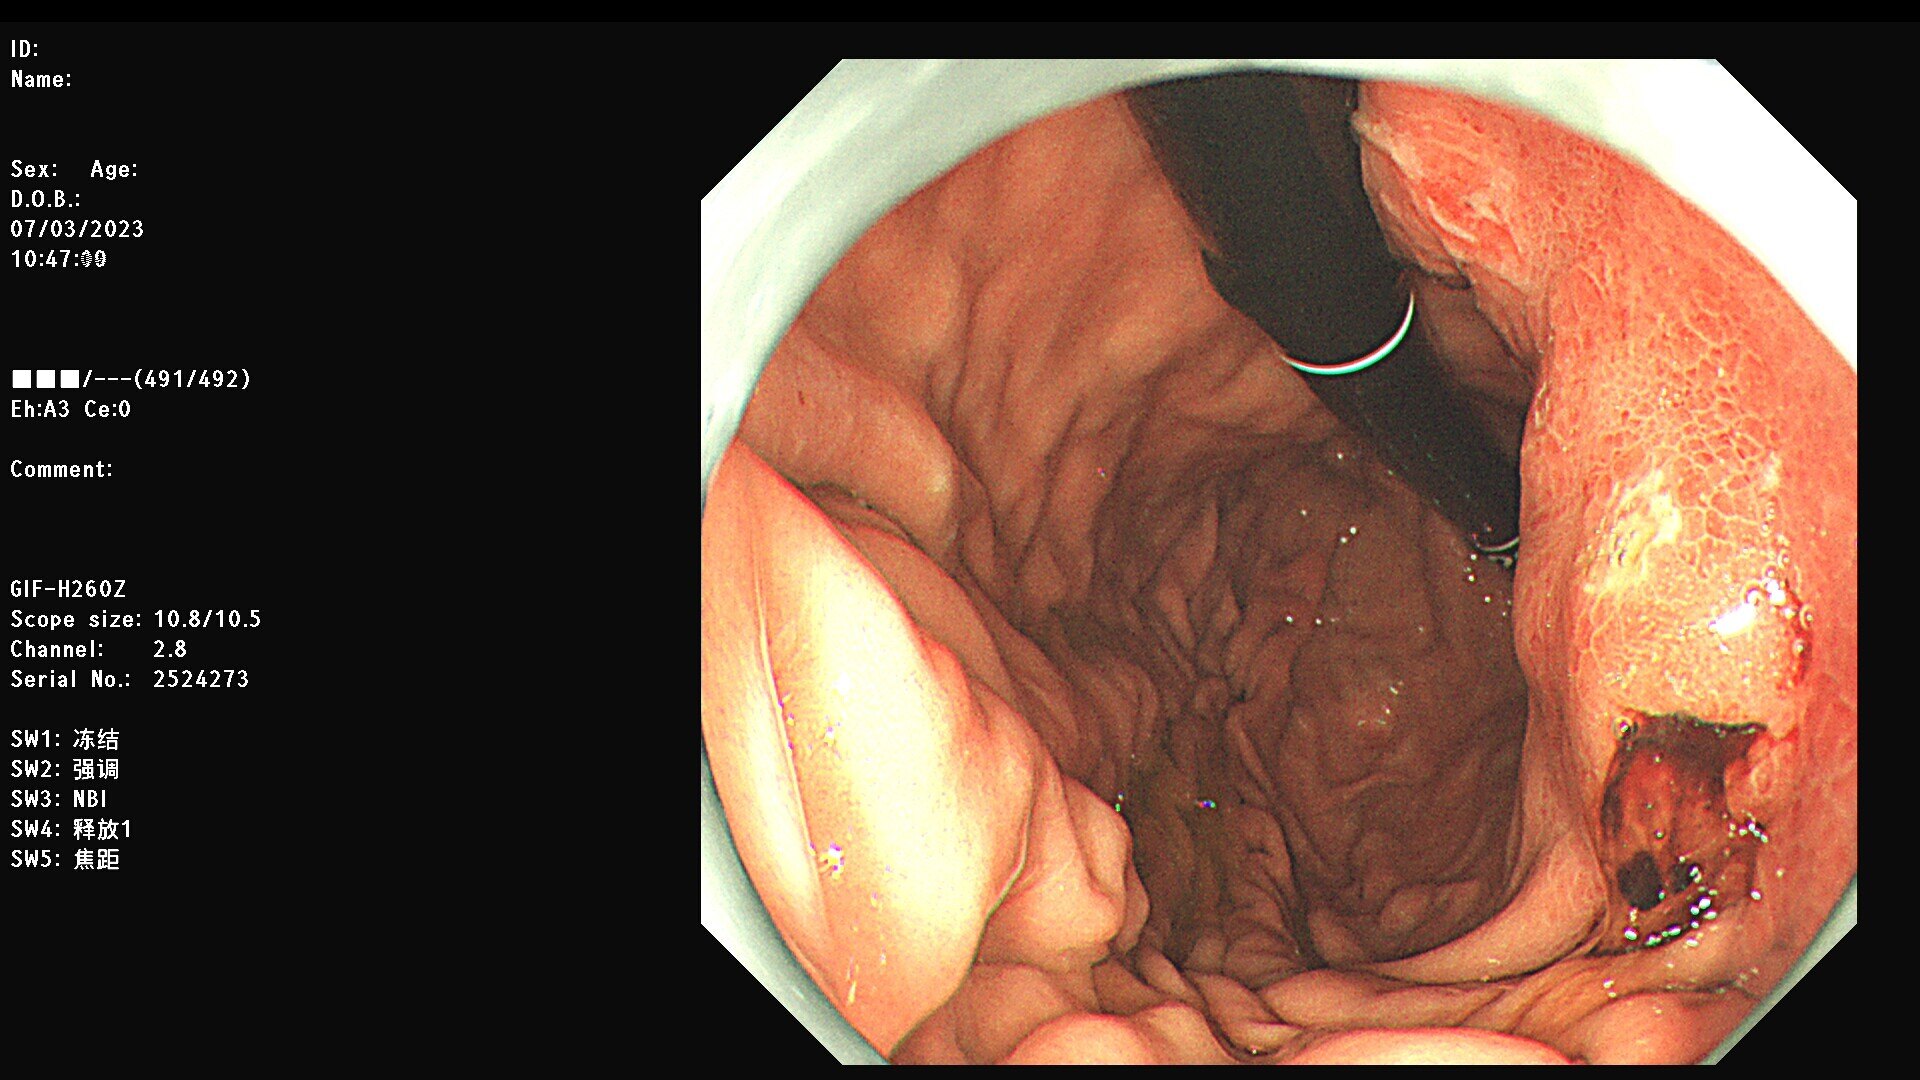

胃体粘膜下肿物,疑似低分化癌

患者76岁老年男性,外院CT提示胃体恶性肿瘤。我院行放大胃镜检查。见胃体中下部粘膜下隆起样改变,皱襞僵硬,胃腔缩小,表面腺体似乎有融合,但未见明显肿瘤性血管,病灶中央见一处约0.6cm溃疡样凹陷,内镜怀疑低分化癌。后活检病理回报倾向平滑肌肉瘤。平滑肌肉瘤较为罕见,从医十多年,这是第一例。活检时往溃疡基底及边缘深挖活检,阳性率会高一些,当然出血风险也会增大。